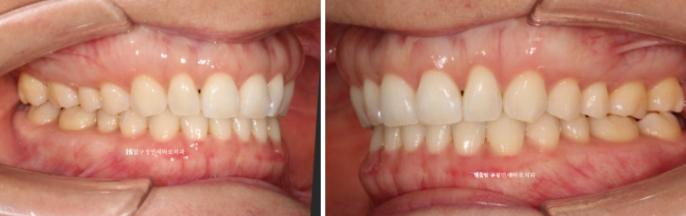

23.07~24.05

가위교합이었던 우측 상악 제 2대구치 교합도 잘 유지가 되고 있습니다.